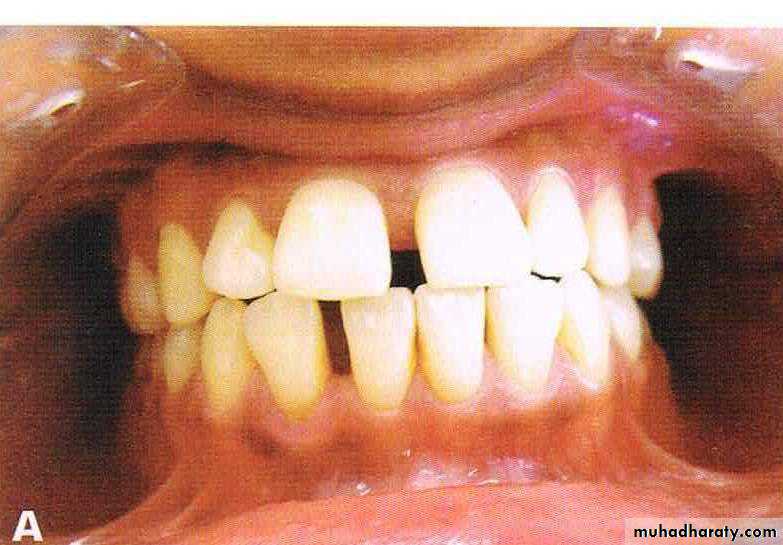

Before & after treatment

Fig: Midline diastema

Fig: Spacing73